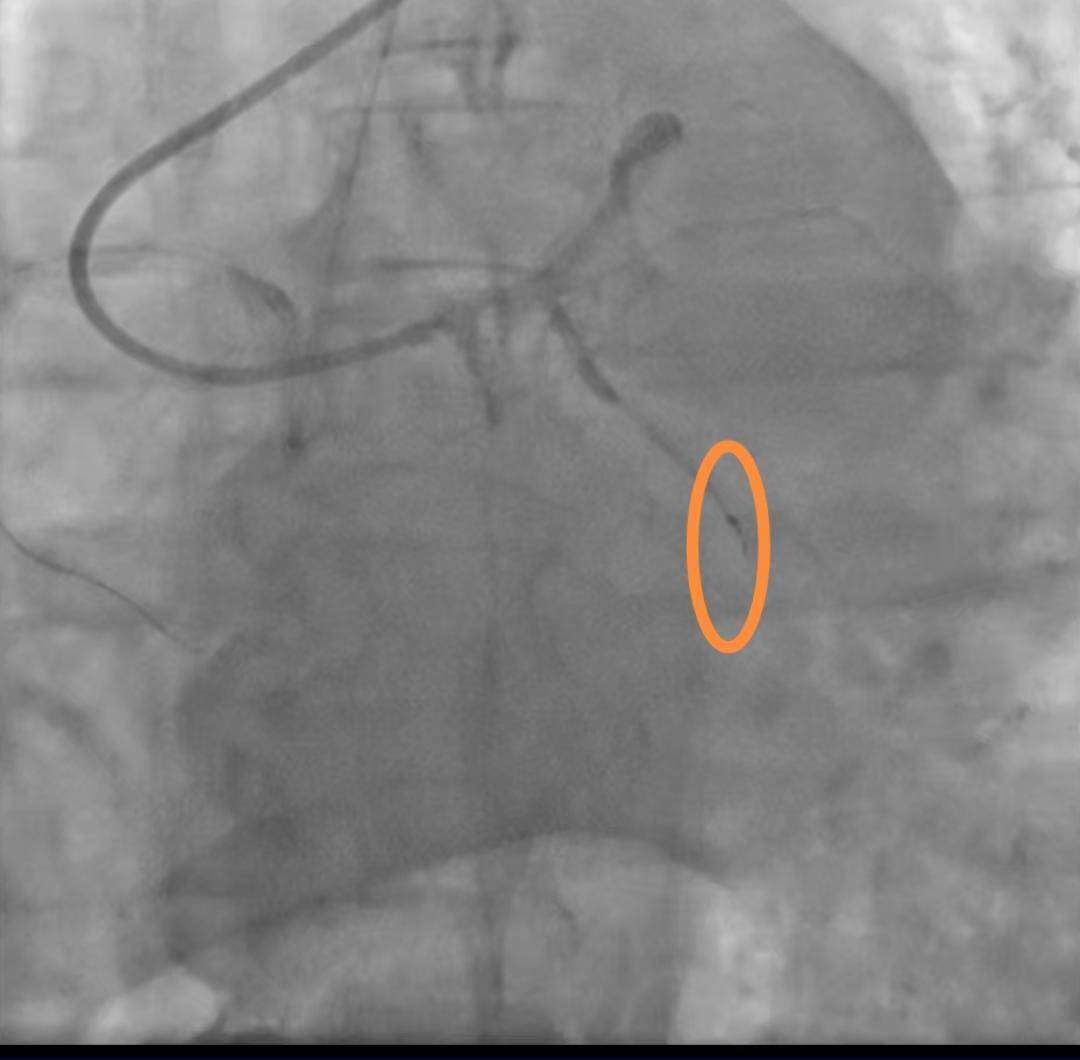

老人手术时导丝断裂掉进血管 医院:外科取出意义不大,补偿8000元

封面新闻记者 石伟 9月28日,河南汝州的高女士反映,她的父亲在河南省胸科医院手术时,手术用的导丝末端断裂,一截2厘米左右的导丝被遗留在血管中。 断裂的导丝(...